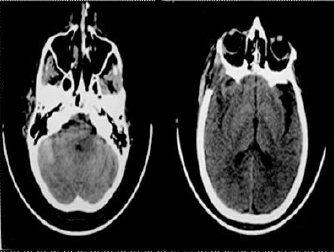

El cuidado postquirúrgico de la paciente se realizó en la unidad de cuidados intensivos. Durante el primer día postquirúrgico presentó deterioro neurológico con crisis consistente en mioclonías del miembro superior derecho, alteración de la interacción con el medio y aumento del lenguaje perseverante. Por este motivo, se ordenó un TAC de cráneo en el que se observaron cambios postcraneotomía, resección tumoral completa, edema cerebral hemisférico derecho y colección subdural derecha que ejerce un leve efecto compresivo sobre los tejidos aledaños (figura 2).

Figura 2. Se repite TEC cerebral, sin cambios importantes respecto al estudio anterior.